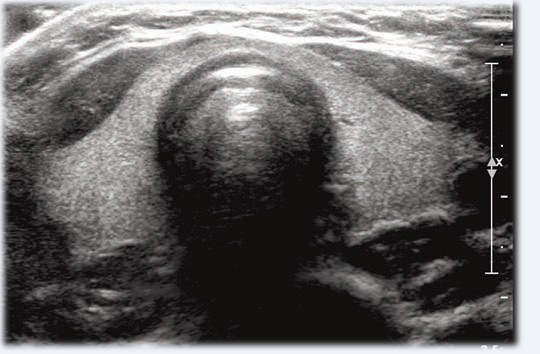

L’échographie de la thyroïde permet d’analyser la taille, la structure et l’aspect de la glande thyroïde, ainsi que les ganglions situés dans le cou. Cet examen permet au médecin de détecter des nodules, une inflammation, une anomalie de volume ou toute autre modification nécessitant une surveillance.